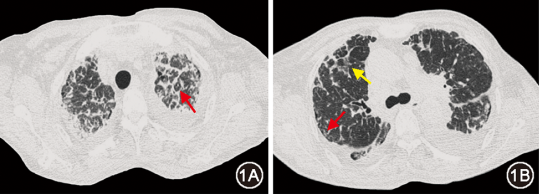

图2  治疗前(2024年9月10日)胸部CT:双侧胸腔积液(图2A箭头)、胸膜增厚(图2B红箭头),纵隔多发肿大淋巴结(图2B黄箭头)

本例患者影像表现为支气管血管束增粗、小叶间隔增厚、磨玻璃及网格影,呈“淋巴道分布模式”,伴纵隔淋巴结肿大、胸膜增厚及胸腔积液。在接诊“淋巴道分布模式”的肺间质病变患者时,应鉴别癌性淋巴管炎、结核感染、结节病等疾病。患者虽为老年女性,有右乳肿大,但病情发展相对缓慢,影像提示淋巴水肿,故除外癌性淋巴管炎。患者T-SPOT.TB阳性,纵隔淋巴结病理见炭末沉积,伴多核巨细胞,在难以明确诊断时,接受诊断性抗结核治疗,然而效差,除外结核感染。患者影像也符合结节病表现,且血ACE升高,对结节病有一定提示意义,但结节病中ACE阳性率不足50%,其他疾病如肺结核也可升高,故其阳性不能作为结节病诊断标准[1, 2];此外,患者伴顽固性胸腔积液,在结节病中少见[3];BALF淋巴细胞占比低,激素治疗无效,排除结节病诊断。此外,尘肺病及肺淋巴管疾病亦有类似表现,应予鉴别。

肺间质病变较少合并胸腔积液,本例患者的胸腔积液也为鉴别要点。其胸腔积液性质介于渗漏之间,单核细胞为主,与心脏舒张功能减低无关,亦无明确肿瘤和结核感染证据,虽然患者存在淋巴回流障碍,但并非乳糜胸。而淀粉样物质可沉积于胸膜,影响液体吸收,引起胸腔积液。